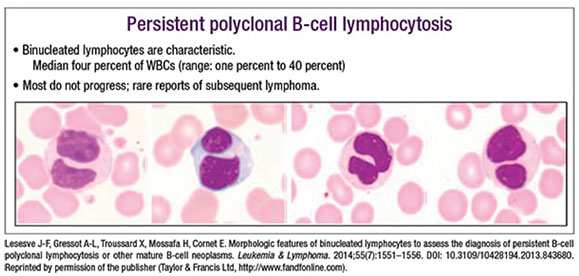

Persistent polyclonal B-cell lymphocytosis may persist for decades, and is associated with female smokers

- median lymphocyte count is 5.5 x 10^9, not very high

- polyclonal increase in IgM is another common findings, and 1/3 of cases have gain of isochromosome 3q

- morphologically, can see beautiful binucleated lymphocytes (different from pertussis)